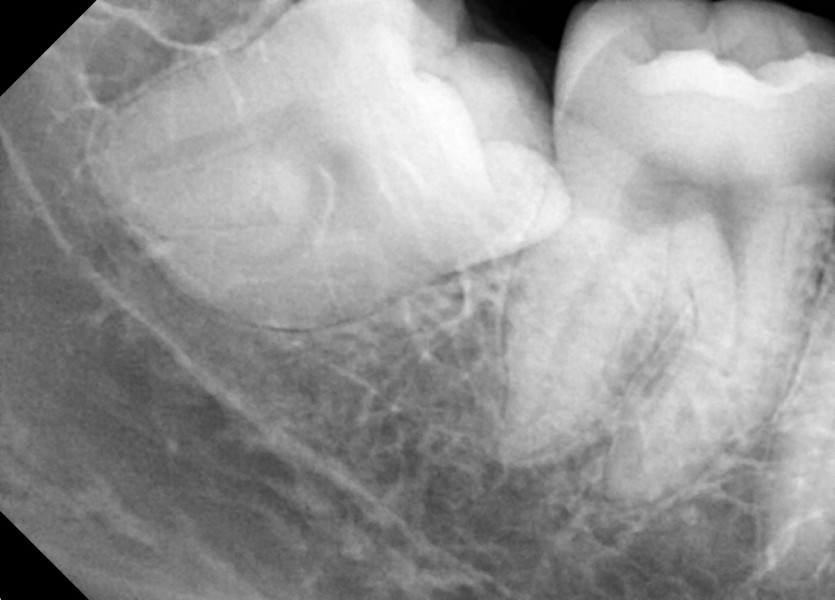

#18,28,38,48 사랑니 발치

구강 외과 전문의가 당일 발치했습니다.